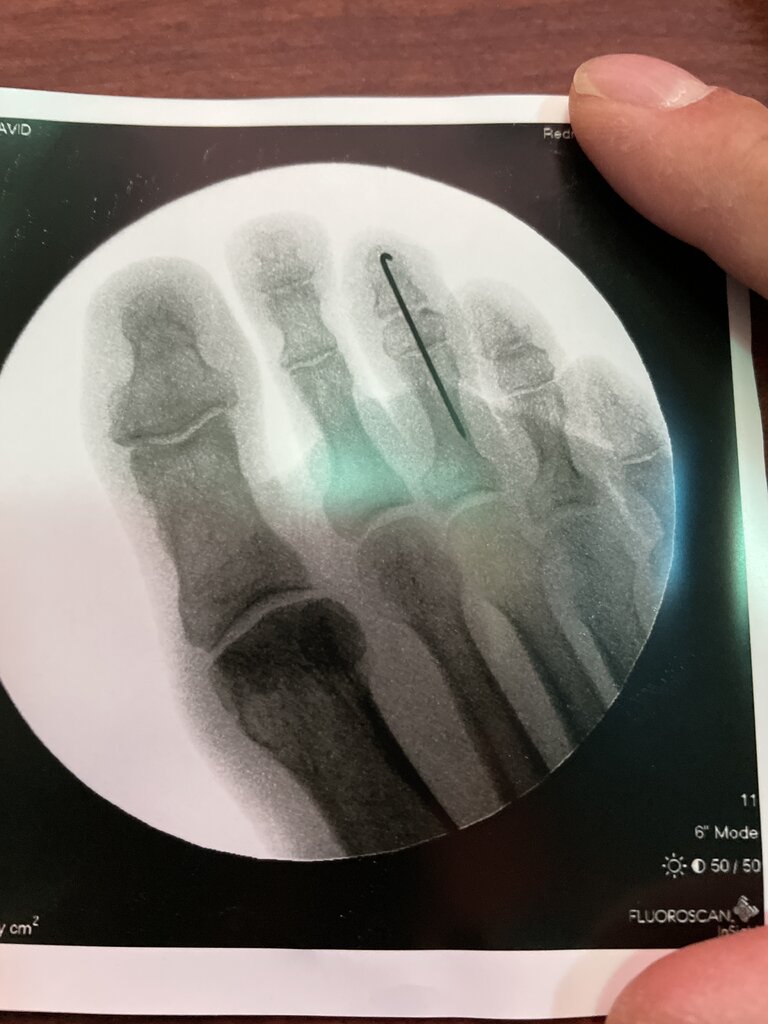

Do patient's complain about feeling the end of the K-wire ever even though it is bent?I like to bend and bury a K wire. They’re easy to remove under local anesthesia in the office later if the patient wants/needs it out. I always angle the “hook” part laterally so it’s easy to locate during removal

View attachment 361867View attachment 361868

If the hook hugs the bone they don't feel it. If the wire migrates distally then they will, in which case I'll remove it in the office.Do patient's complain about feeling the end of the K-wire ever even though it is bent?

Procedure:

1. Drill pilot hole in proximal phalanx with the wire

2. Send the wire distally through middle and distal phalanges

3. Retrograde the wire into the proximal phalanx all the way then reduce the hammertoe

4. Distract the wire out about 5mm-10mm

5. Bend wire where it exits the skin then cut to size

6. Make small incision laterally at the tip of the toe

7. Drive wire back into the toe and tamp. The tamping seats the hook of the wire against the distal phalanx and at the same time ensures that the PIPJ arthrodesis surfaces are in firm contact.